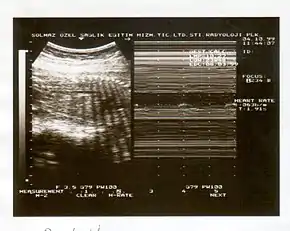

A biophysical profile (BPP) is a prenatal ultrasound evaluation of fetal well-being involving a scoring system,[1] with the score being termed Manning's score.[2] It is often done when a non-stress test (NST) is non reactive, or for other obstetrical indications.

The BPP has five components: four ultrasound (US) assessments and an NST. The NST evaluates fetal heart rate and response to fetal movement. The five discrete biophysical variables are:

1. Fetal heart rate

5. Amniotic fluid volume